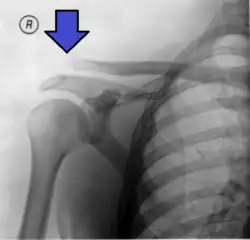

This is a more severe form of a type III injury, with the trapezial and deltoid fascia stripped off of the acromion as well as the clavicle. This is type III but with exaggeration of the vertical displacement of the clavicle from the scapula. There is a 2- to 3-fold increase in the coracoclavicular distance, causing such a severe displacement that the clavicle almost pierces the skin.[11] The humerus and scapula drop without having the clavicular strut to lift them, which manifests as a severely drooping shoulder.[11] This injury generally requires surgery.[5] Distinguishing between Type III and Type V separations on imaging can be unreliable.[12]

X-ray indicates a separated shoulder when the acromioclavicular joint space is widened (it is normally 5 to 8 mm).[9]